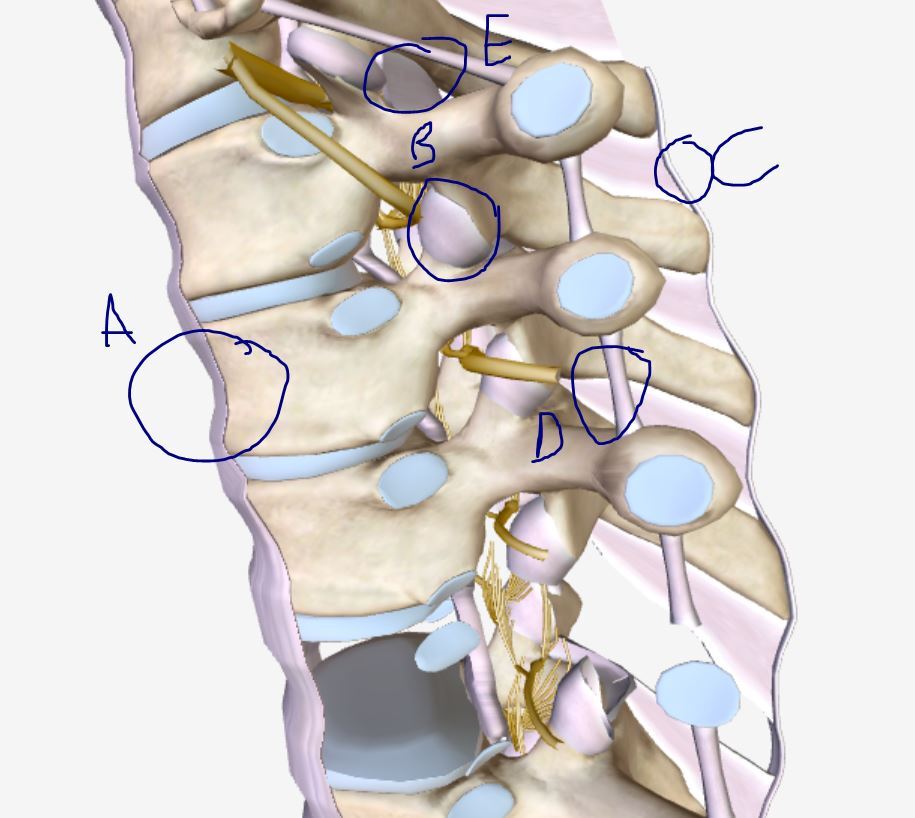

label these spinal ligaments

A) anterior longditudinal

B zygopophyseal

C supraspinous

D intertransverse

E flavum